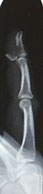

Des ruptures tendineuse sans plaies traumatiques font parties des pièges diagnostiques en chirurgie de la main et doivent être recherchées devant une perte de la flexion active de P3, « jersey finger » qui correspond à une désinsertion du tendon fléchisseur profond de la base de P3 (typique des sports d’arrachage de maillot, rugby,  …..). Le diagnostic est clinique mais doit être complété par l’imagerie (Rx et échographie) pour exclure un arrachement osseux conséquent nécessitant une ostéosynthèse d’emblée (photo radiographie)

fracture arrachement du tendon fléchisseur profond au niveau

de son site d'insertion sur la base de la dernière phalange